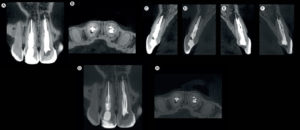

La reabsorción cervical invasiva (RCI) es una complicación patológica grave, una forma poco frecuente y a menudo agresiva de reabsorción radicular externa que incluye dientes

La tomografía computarizada de haz cónico (CBCT) ha promovido cambios en los enfoques en endodoncia y ha mejorado la toma de decisiones en casos clínicos